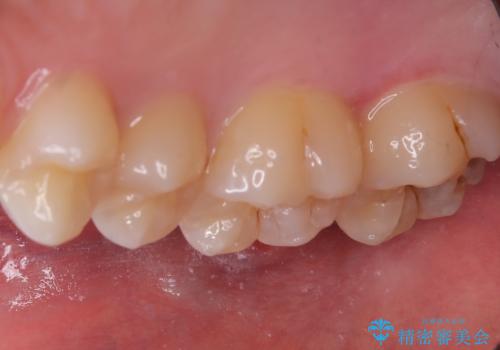

左上一番奥の歯の頬側に実質欠損を伴う虫歯が存在したため、セラミックインレーでの治療となりました。

上顎左側第二大臼歯頬側面から遠心面、咬合面にもう蝕が波及していたためアンレー形態となりました。

清掃しずらい箇所ではあるため、汚れが付きづらい適合性のよいセラミック素材を選択しました。

セラミックアンレーセット時、ラバーダム防湿を行っています。